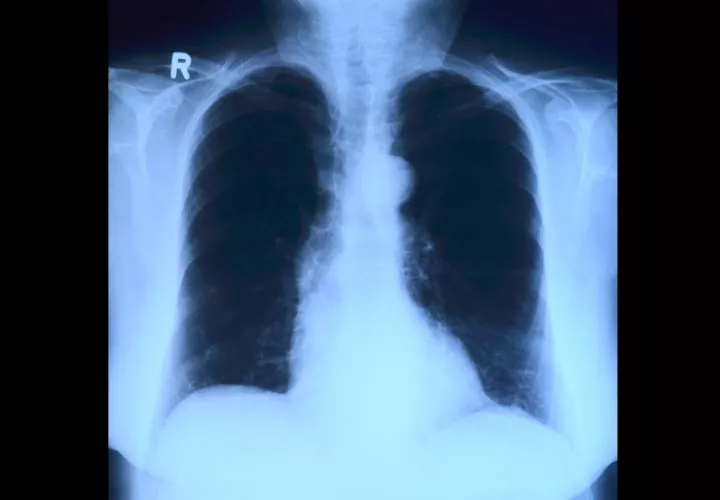

Científicos de Google y de la Universidad estadounidense de Northwestern han desarrollado un sistema de inteligencia artificial capaz de detectar cáncer de pulmón mejor que los radiólogos, lo que podría favorecer el diagnóstico temprano de un tumor que al año mata a más de un millón de personas en el mundo.

Basándose en esto, los científicos estadounidenses desarrollaron un algoritmo capaz de detectar nódulos pulmonares malignos, a veces minúsculos, a partir de resultados de un TAC -tomografía axial computarizada- del tórax, con un empeño y precisión igual o mejor que el de los radiólogos.

Para ello, "entrenaron" al sistema en 42.290 imágenes de tomografía computarizada y encontraron que el sistema de inteligencia artificial fue capaz de detectar los módulos con una precisión del 94% en 6.716 casos de prueba.